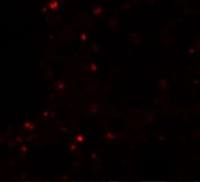

C1s antibody detects C1S protein at Golgi apparatus by immunofluorescent analysis.

Sample: HeLa cells were fixed in ice-cold MeOH for 5 min.

Green: C1S protein stained by C1s antibody (GTX105464) diluted at 1:500.

Blue: Hoechst 33342 staining.